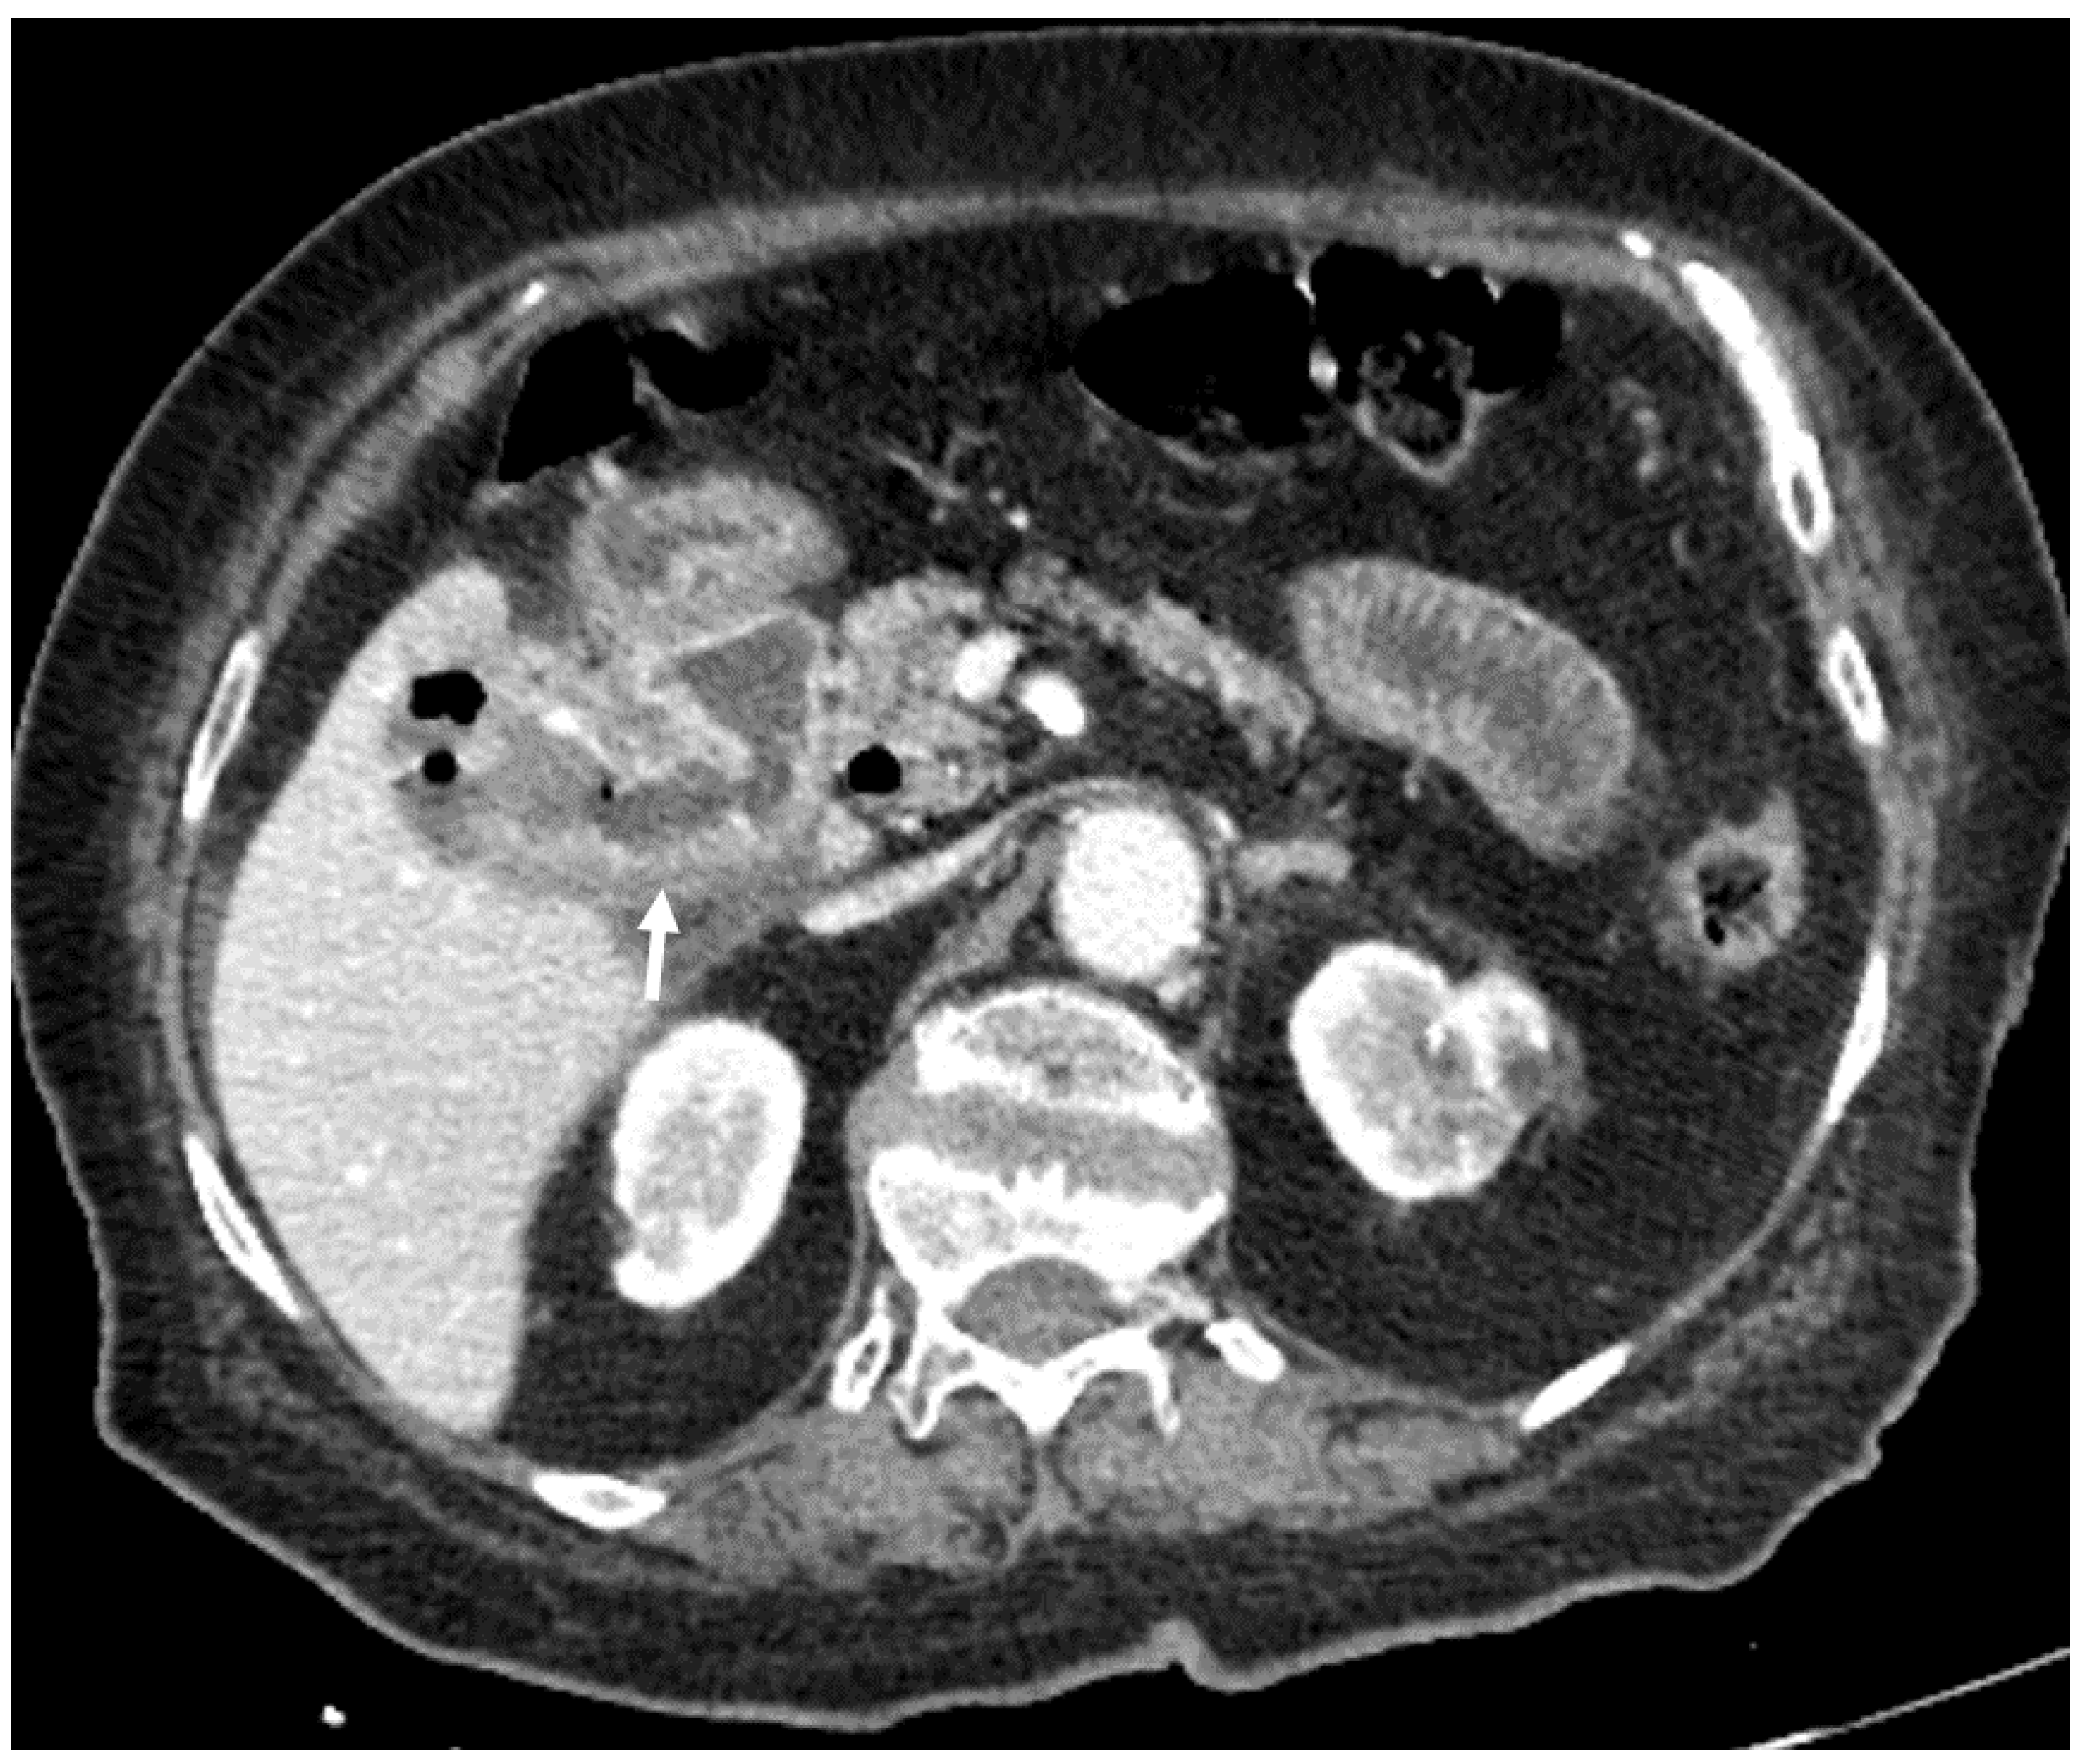

| F, 82 | 25 | III | Laparoscopically assisted enterolithotomy | 95 | Ileum | 3 × 3 cm | 3 | 14 | Good: recovery |

| F, 48 | 40 | III | Laparoscopically assisted enterolithotomy | 70 | Ileum | 3 × 4 cm | - | 10 | Good: recovery |

| F, 85 | 47 | IV | Laparoscopically assisted enterolithotomy | 60 | Ileum | 4 × 3 cm | 12 | 13 | Good: recovery |

| F, 87 | 2 | IV | Laparotomy with enterolithotomy | 35 | Jejunum | 4 × 3 cm | 5 | 7 | Poor: death |